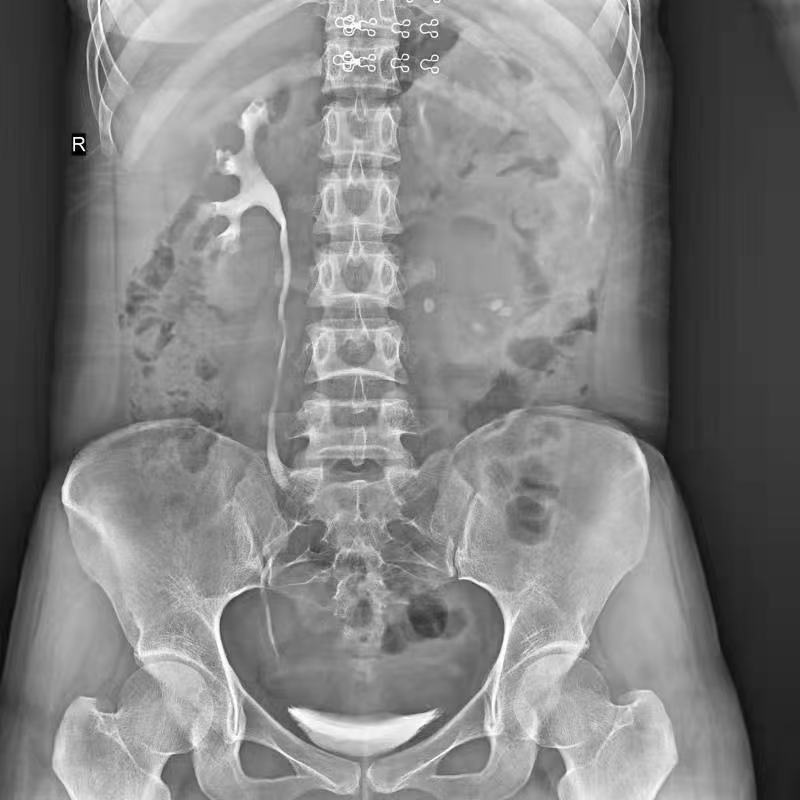

● 獨特實用的床面升降功能,有利于DR攝影及行動不便的患者上下床;

● 床面可降至與病床平行高度,既方便醫(yī)護人員平移患者,又避免對患者的二次傷害;

● 對于醫(yī)生的近臺操作也更方便,不同身高的醫(yī)生可根據(jù)需要調(diào)節(jié)床體高度,更利于醫(yī)生開展相關(guān)近臺手術(shù)。

拉伸自如:SID電動拉伸,最長可延伸至1.8米,滿足放射科室各種拍片距離的需求。如:GBZ 70-2015職業(yè)性塵肺病的診斷標準中對胸片拍片距離1.8米的要求。